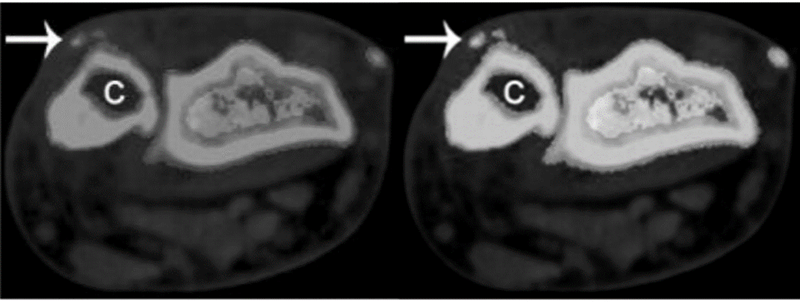

图2.双能计算机CT断层扫描显示远尺桡关节焦磷酸钙沉积